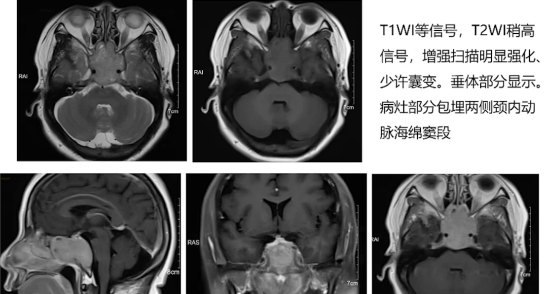

2) 头颅MRI增强扫描:病灶呈长T1长T2信号,增强扫描明显强化,内见无强化小囊变,垂体部分显示,病灶部分包绕双侧颈内动脉海绵窦段。